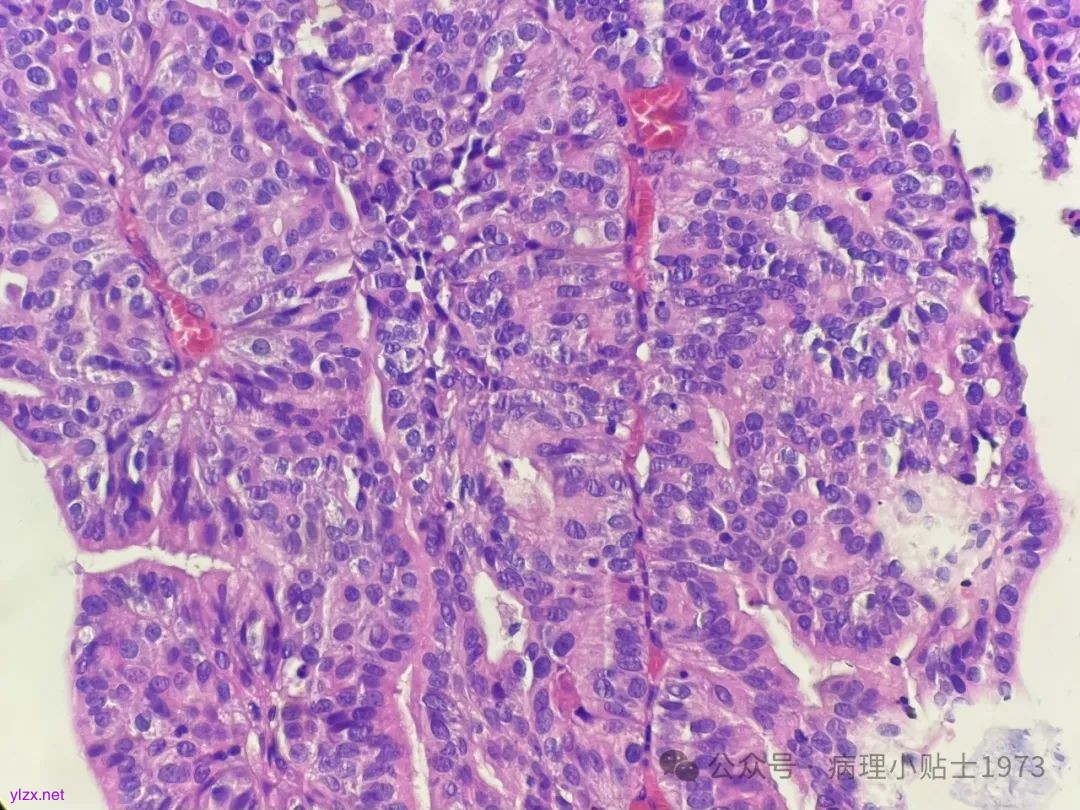

问题一:本病例出现了显著的腺性分化,不要误诊为单纯的腺癌。仔细寻找,仍然可以见到复层排列的经典尿路上皮癌成分。

问题二:本病例的肿瘤极性轻度紊乱,细胞核轻度到中度异型,部分可见清晰小核仁清晰,凋亡易见,免疫组化弥漫表达p16和CK20(弥漫阳性多见于高级别病变),ki67指数较高。到底该归入低级别还是高级别病变呢?

所以,这个病例虽然形态上够不上WHO标准的高级别,但由于其广泛腺样分化,灶区核仁清晰,凋亡易见,弥漫表达p16 和CK20,ki67指数较高,不知能否将其归入高级别非浸润性乳头状尿路上皮癌 (G2)(ISUP分级)。